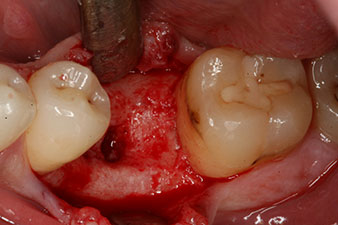

Sechs Wochen nach Extraktion zeigte sich jedoch nach Präparation des Mukoperiostlappens im Bereich der ehemaligen mesialen Alveole eine unvollständige Ossifikation.

Nach gründlicher Entfernung des Granulationsgewebes wurde das Implantat wie geplant eingebracht (blueSky, bredent).

Das Drehmoment beim maschinellen Einbringen war 43 Ncm. Zusätzlich wurde, nach Einschrauben eines speziellen, auf das Implantatsystem abgestimmten Mess-Pfostens (SmartPeg), der ISQ-Wert mit der Sonde des W&H Osstell ISQ Modul bestimmt.